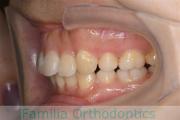

No.22V-244

- 主な症状:

- 上顎前突

- その他の症状:

- 叢生

- 年齢:

- 14歳

- 性別:

- 女性

- 抜歯部位

- 上:

- 44

- 下:

- 8558

- 主な使用装置:

- FEA

- 治療にかかった費用:

- 88万円

上の前歯を治したいとのことで来院されました。かなり強い前歯の突出がありましたので、上下左右から小臼歯を抜歯して、マルチブラケット法を行いました。約2年半、30回程度の通院が必要でした。前歯の移動量が多い上顎前突(出っ歯)の治療は、前歯の歯根吸収のリスクが特に高めです。